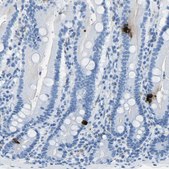

Anti-SST antibody produced in rabbit, a Prestige Antibody, is developed and validated by the Human Protein Atlas (HPA) project . Each antibody is tested by immunohistochemistry against hundreds of normal and disease tissues. These images can be viewed on the Human Protein Atlas (HPA) site by clicking on the Image Gallery link. The antibodies are also tested using immunofluorescence and western blotting. To view these protocols and other useful information about Prestige Antibodies and the HPA, visit sigma.com/prestige.

These images and the collection of this vast data set can be viewed on the Human Protein Atlas (HPA) site by clicking on the Image Gallery link. We also provide Prestige Antibodies® protocols and other useful information.

• IHC tissue array of 44 normal human tissues and 20 of the most common cancer type tissues.